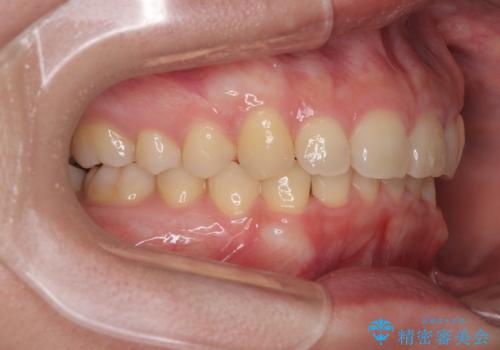

- 下顎前歯が完全に隠れてしまっていることを気にして来院された患者様です。

下顎の臼歯が手前に傾斜していることで咬み合わせが深くなってしまい、下顎前歯が見えないほどに上顎前歯が覆い被さっている状態でした。

下顎臼歯を起き上がらせるためにユーティリティーアーチを使用し、一気に深い咬み合わせを改善することができました。